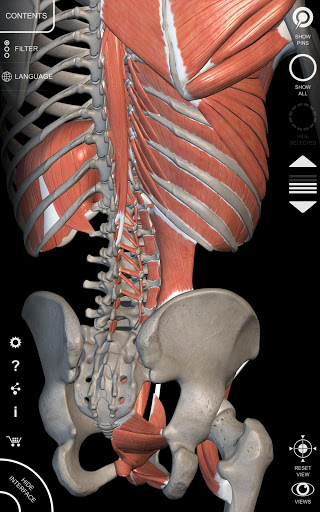

"Anatomy 3D Atlas" vous permet d'étudier l'anatomie humaine de manière simple et interactive.

Grâce à une interface simple et intuitive, il est possible d'observer chaque structure anatomique sous n'importe quel angle.

Les modèles anatomiques 3D sont particulièrement détaillés et avec des textures jusqu'à une résolution de 4k.

La subdivision par régions et les vues prédéfinies facilitent l'observation et l'étude de parties individuelles ou de groupes de systèmes et les relations entre différents organes.

• Système musculo-squelettique

• Faites pivoter et zoomez chaque modèle dans l'espace 3D

• Visualisation des muscles à travers des niveaux de couches depuis les plus superficielles jusqu'aux plus profondes